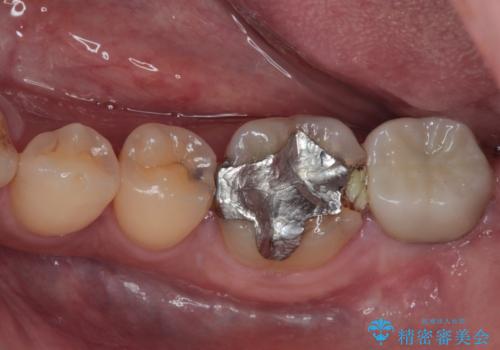

- 左下の歯が欠けてしまったとのことで来院された患者様です。

大きな銀歯が装着されており、その周りからむし歯が広がっている状態でした。

特に症状はなく、神経組織も健全な状態であったため、むし歯を全て取り切った後にフルジルコニアクラウンにて補綴することとしました。